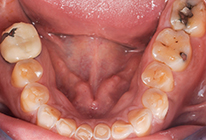

Diagnostic positif et différentiel des formes d’usure

Les conséquences cliniques de l’usure

Thérapeutiques pour les dents faiblement usées